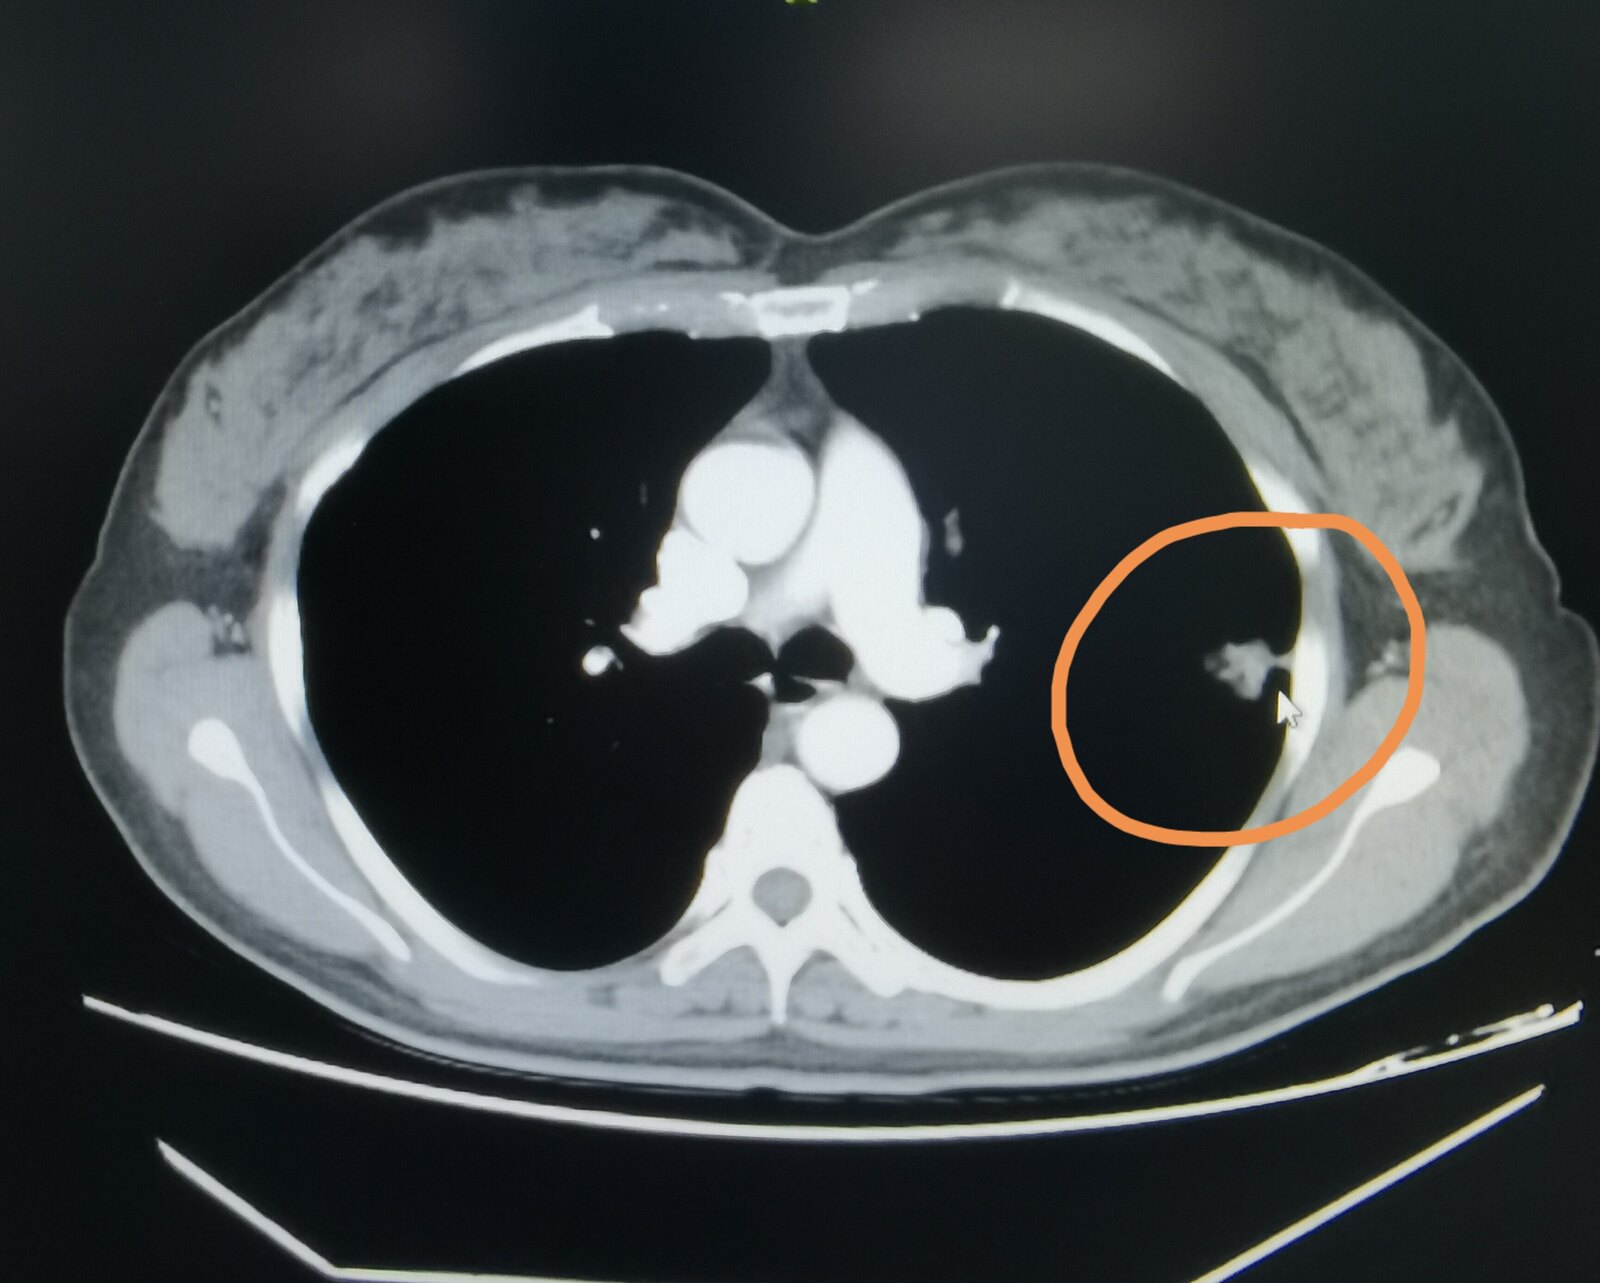

前段时间有一位45岁的女士在丈夫的陪伴下找我看病,她参加了学校组织的体检,刚开始做了一个胸片,胸片显示左肺有阴影,于是她到当地医院又拍了一个CT ,CT发现左上肺有一个结节。

我看到了她当地医院的片子,觉得这个病变首先考虑是肺癌,符合肺癌的CT影像学特征。我建议她住院,系统检查,如果没有禁忌症,这个病变应该手术切除。她回去商量好,给我留言,打算在我这里治疗。我给她安排好床位后,住了进来。经过系统检查,全身没有发现有转移,45岁身体状态肯定也是不错的,于是给她做了手术,手术病理就是显示是一个肺腺癌,其中支气管旁淋巴结有一个已经转移了。

这个女士之前也参加过单位体检,拍的都是胸片,没有发现肺部有问题,我也详细问了这位女士,她是教师,自己不抽烟也没有接触二手烟,也没有肺癌病史的亲人,这么看起来,她并不属于肺癌高危人群。 按照指南推荐,她不需要每年查胸部CT排查肺癌,但就是这样一个没有肺癌高危因素的人,恰恰得了肺癌。 她的病灶不是一两年内长起来的,我觉得要提前三、四年拍CT,就能看到当时比较小的磨玻璃结节, 只不过她之前的从来没有拍过CT而已。通过这个病例给大家一个提示,即便自己不属于肺癌高危人群,如果以前从来没有照过CT,我觉得还是拍个CT留个底儿好一点。 如果肺癌在磨玻璃阶段就把这东西切掉,那治疗效果肯定会很好,不会影响寿命。